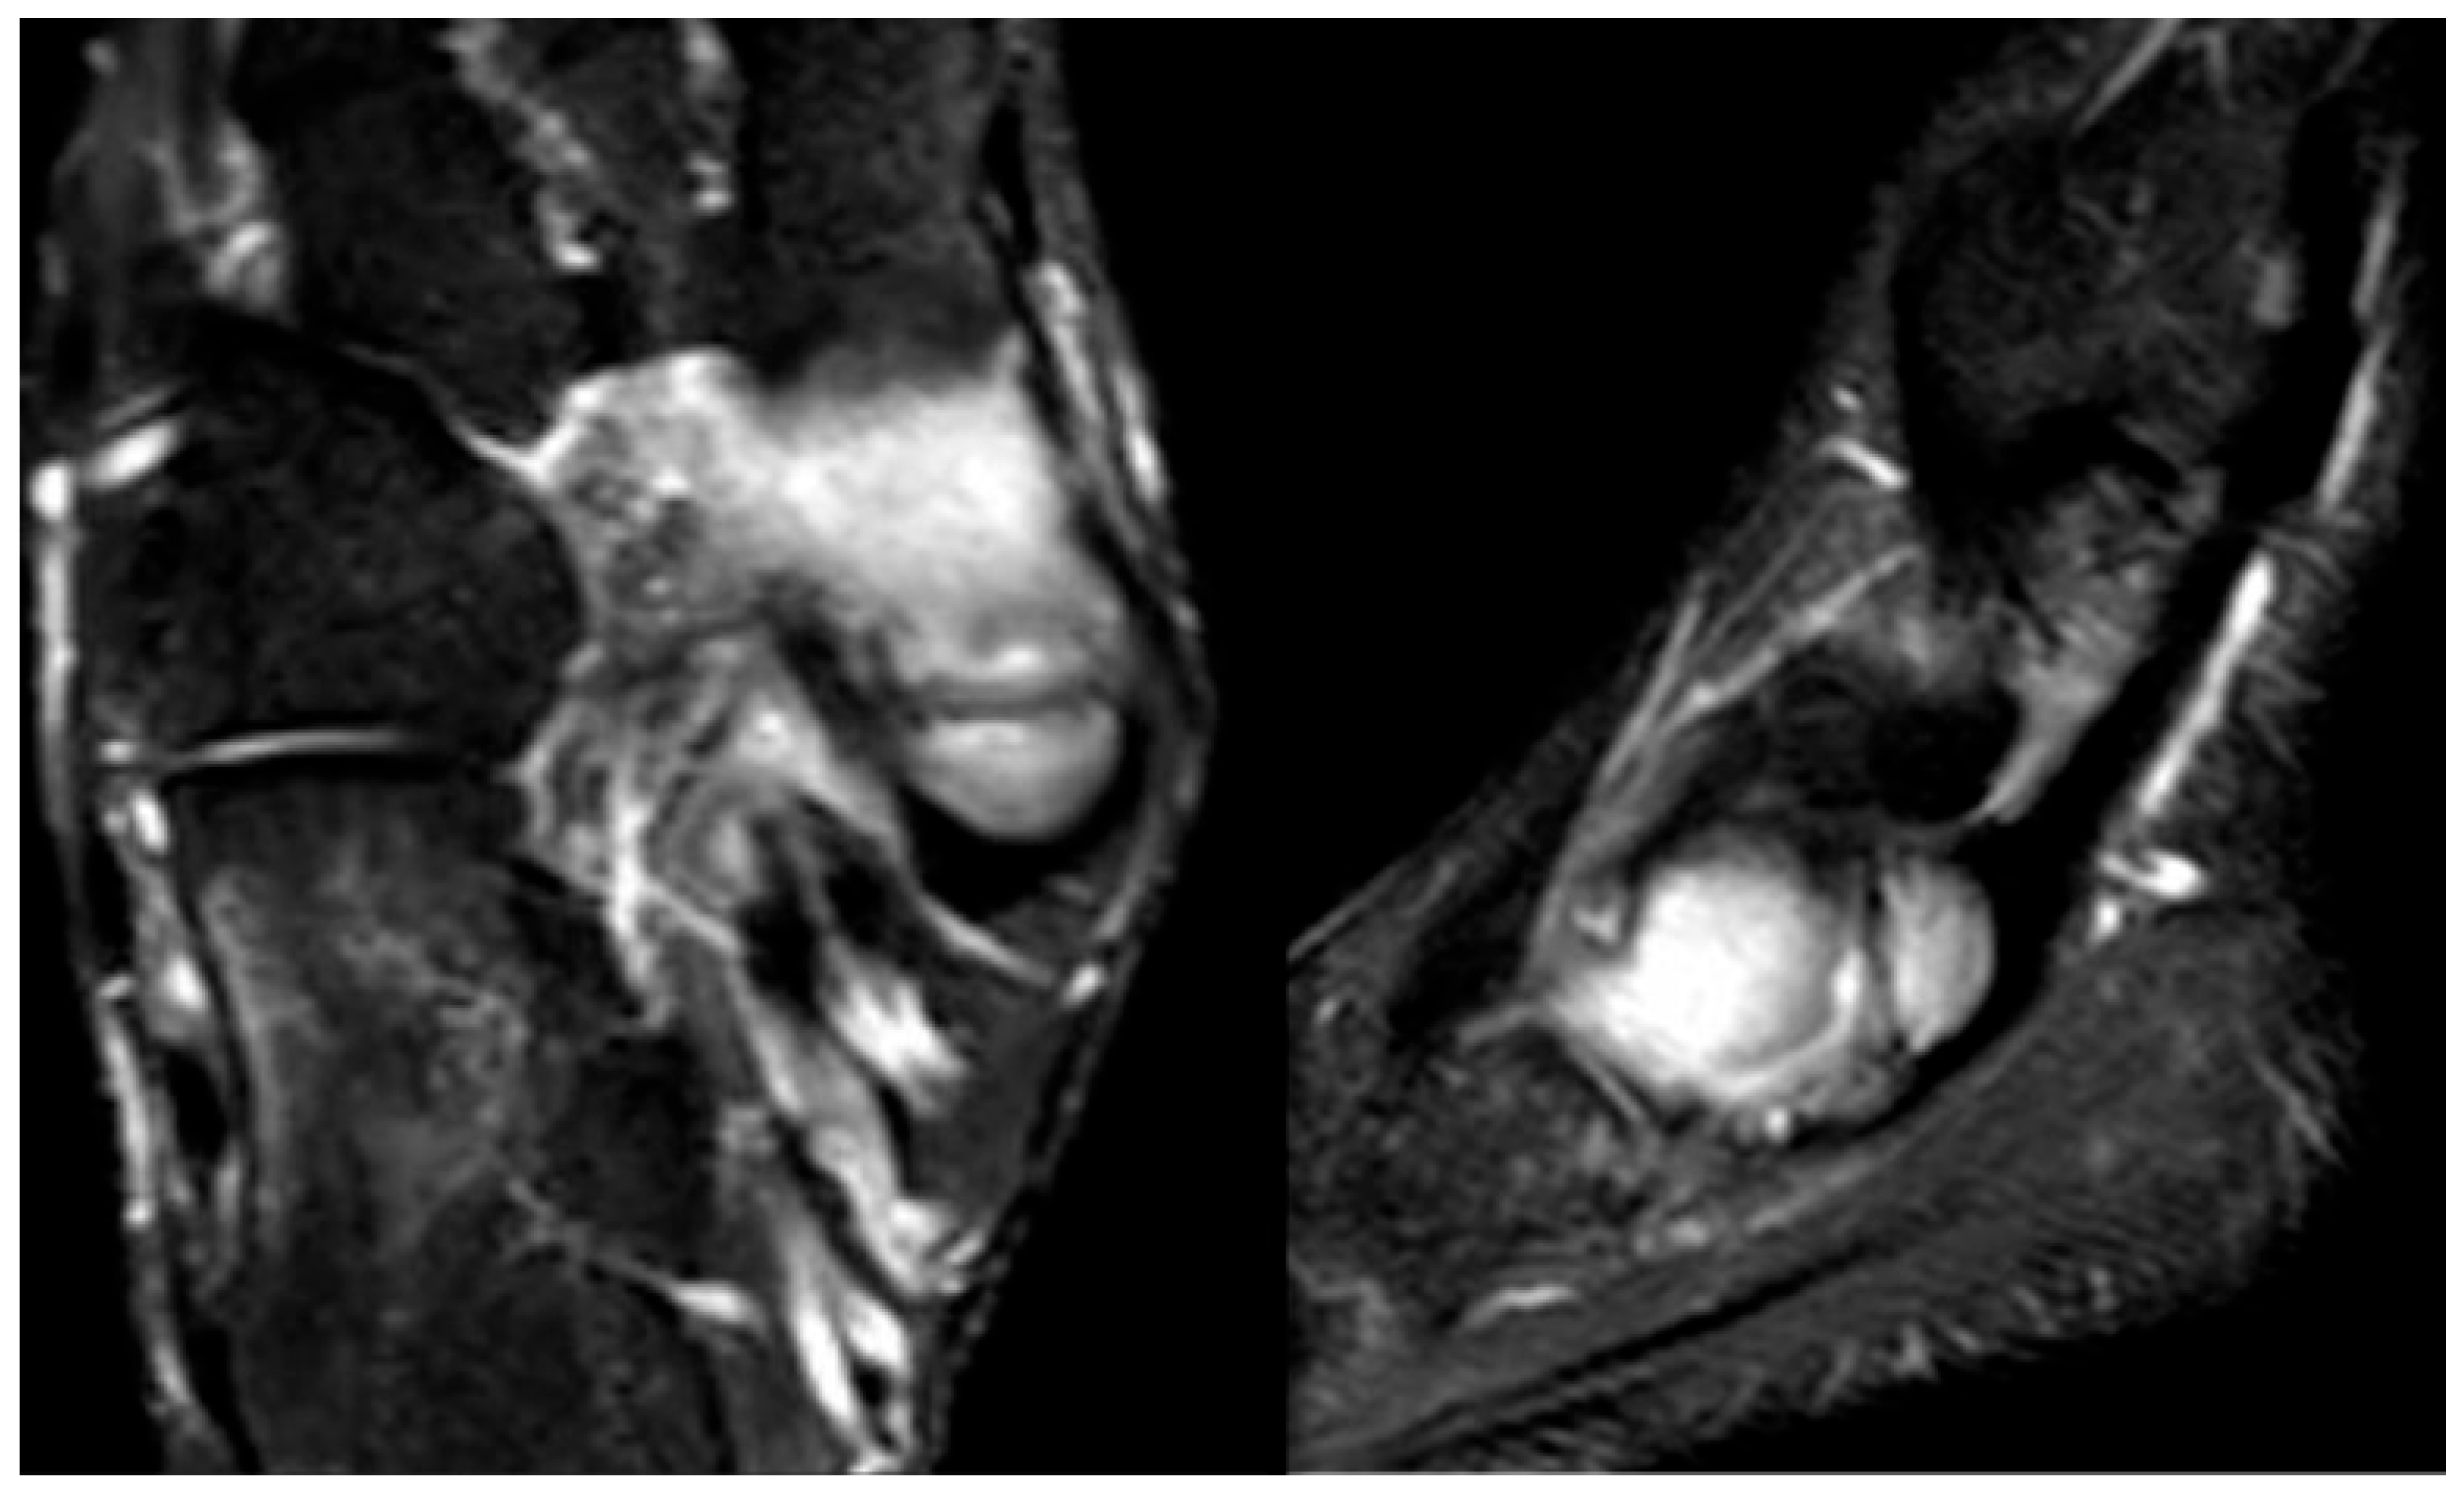

Figure 5.

Twelve-year-old male patient presenting with pain and functional limitation in the absence of trauma. MRI reveals osteochondritis dissecans of the medial talar dome.

As it does not constitute a true osteochondrosis, this condition will not be addressed in detail within this work. However, it has been included for the sake of completeness in the discussion of circulatory-related causes of foot pain, to highlight it as a potential differential diagnosis.